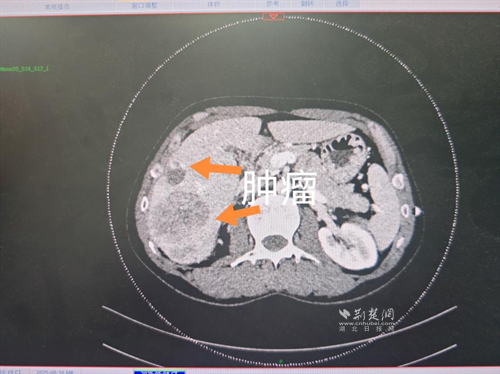

經(jīng)過肝膽外科牽頭組織的多學(xué)科MDT會(huì)診,團(tuán)隊(duì)確認(rèn)其適合接受當(dāng)前國際先進(jìn)的釔90樹脂微球選擇性內(nèi)放射治療。治療僅一個(gè)月后,患者病灶即從10cm縮小至6cm;術(shù)后六個(gè)月復(fù)查顯示,病灶體積進(jìn)一步縮小近40%,影像學(xué)檢查提示完全緩解,臨床分期成功轉(zhuǎn)化,達(dá)到手術(shù)切除標(biāo)準(zhǔn)。